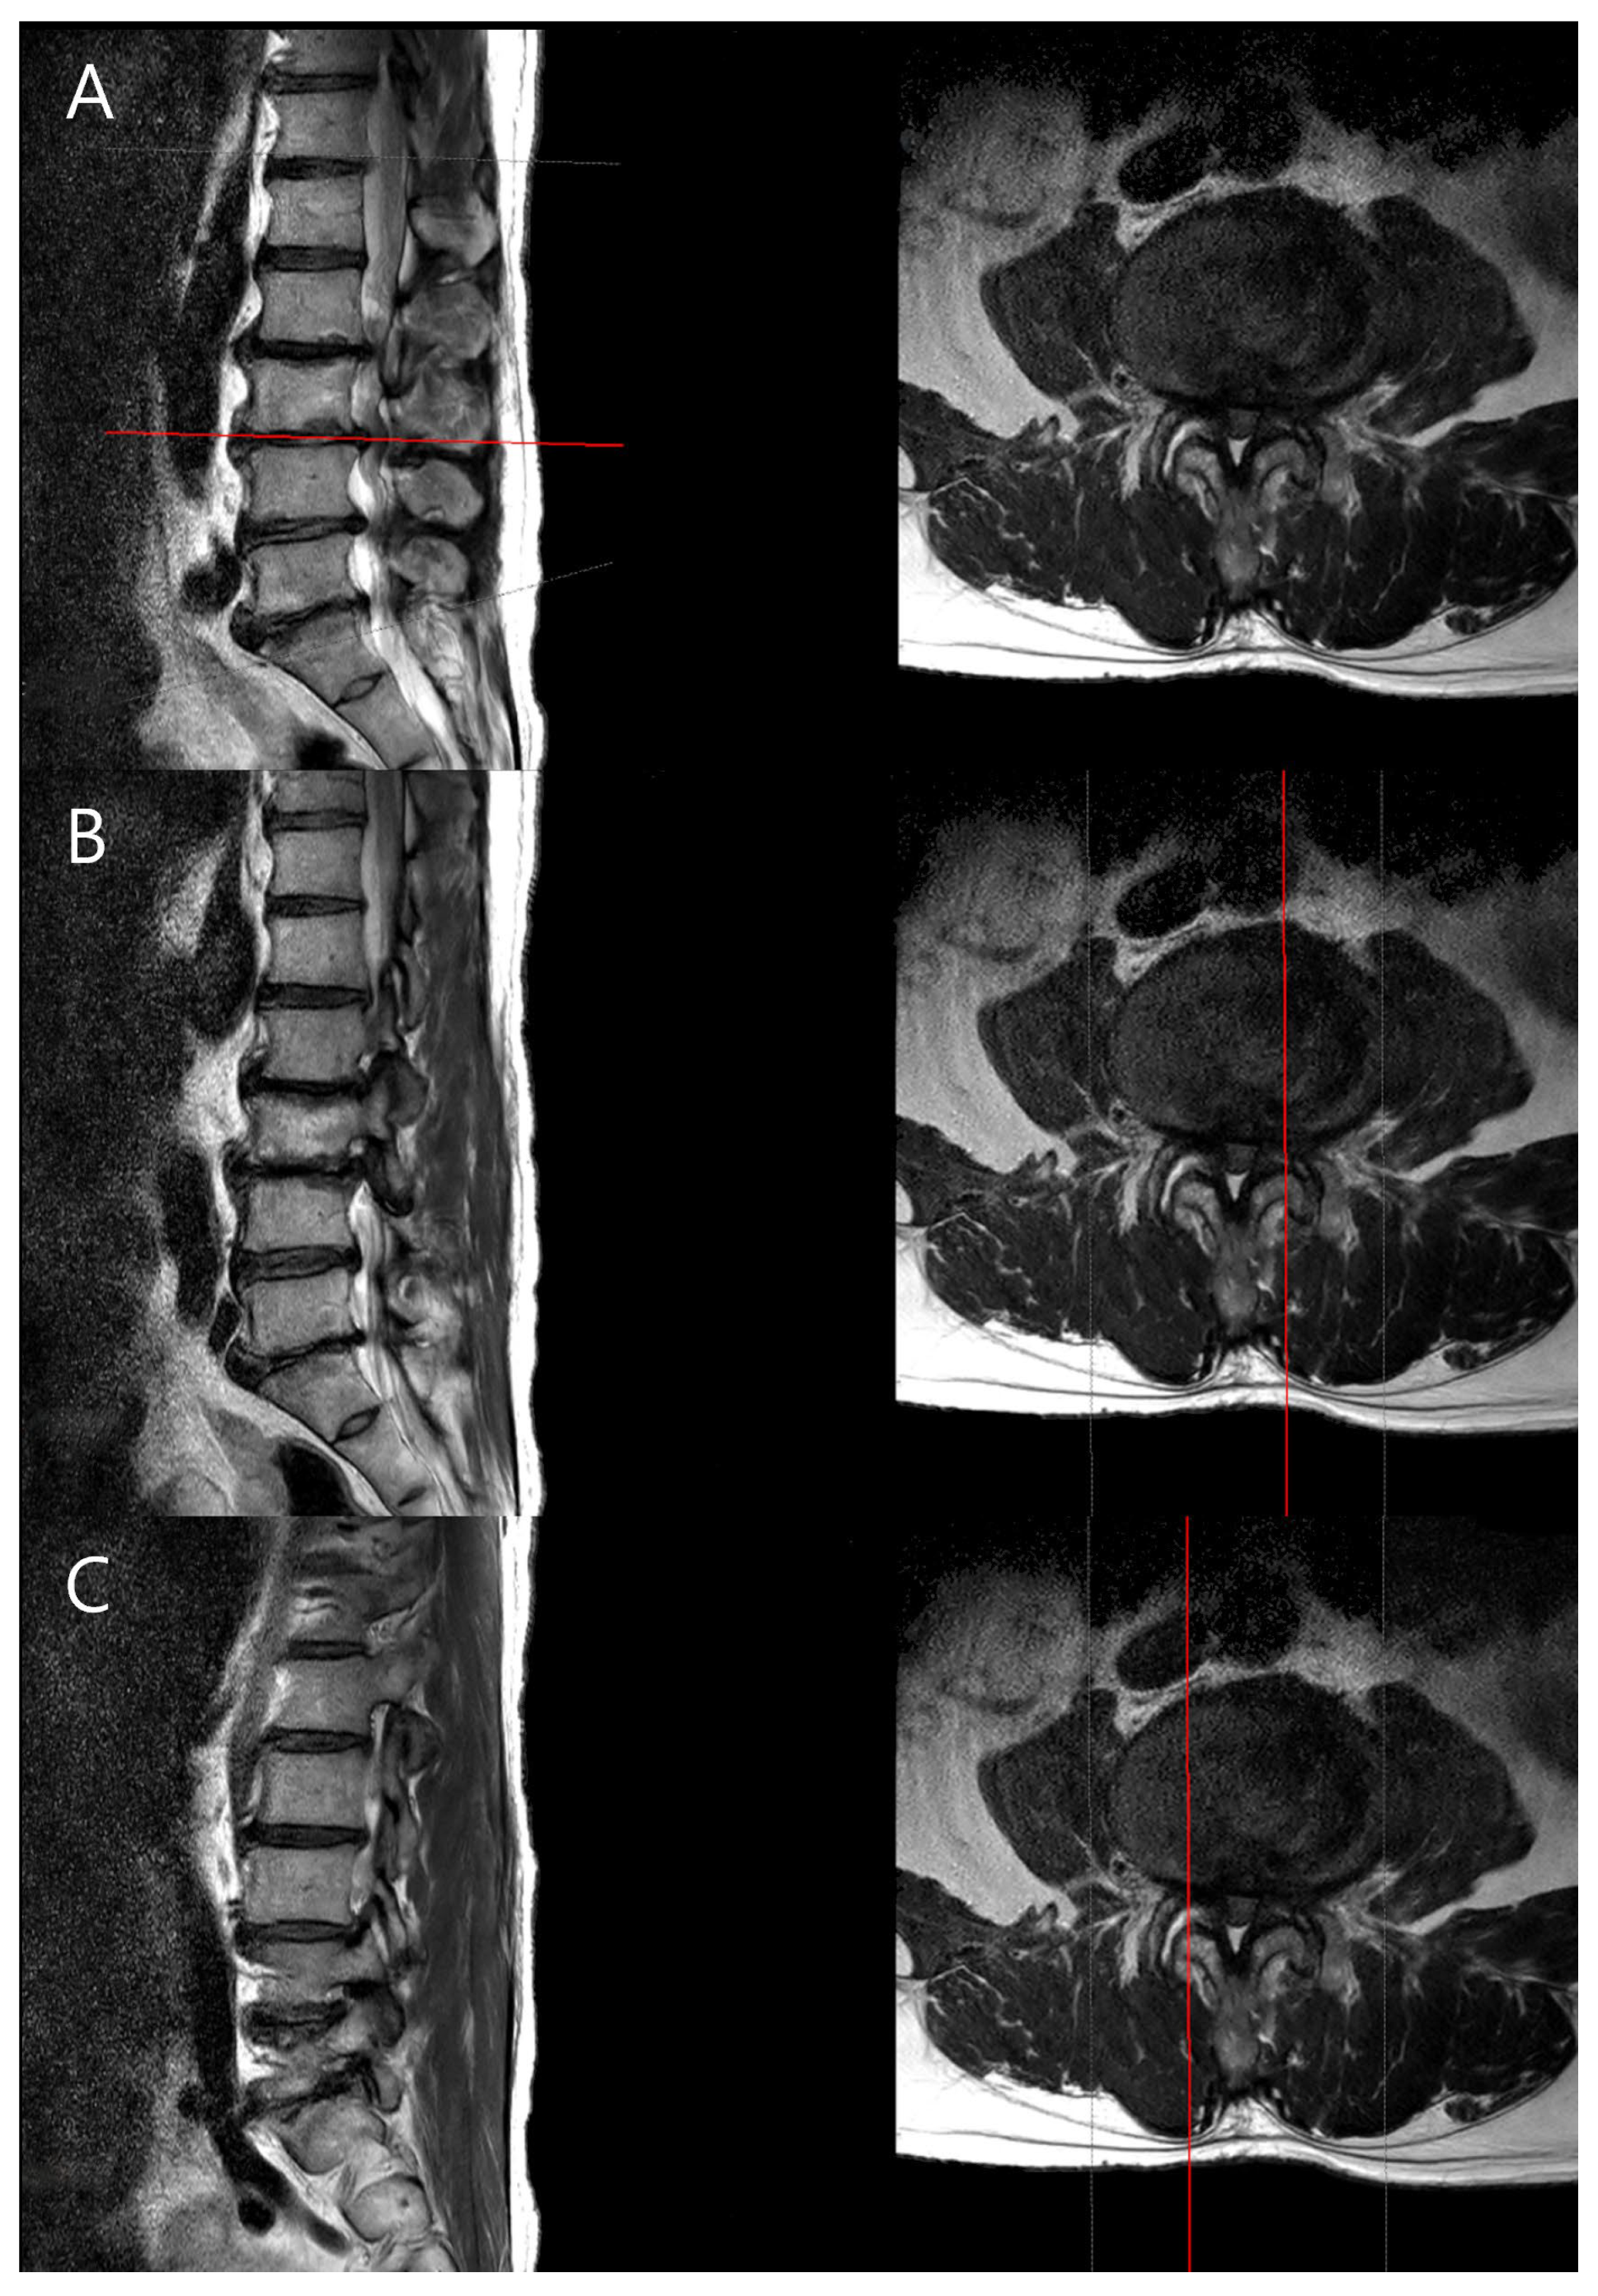

Measurement of spinal parameters: The MRIs of the lumbar spine were performed on a 3.0-T scanner (SIGNA Premier, GE Healthcare, Chicago Illinois, USA) with a spine array coil. Intervertebral disc degeneration was graded using the Pfirrmann classification system based on T2-weighted sagittal images [13]. Foraminal stenosis was assessed using the Lee grading system, primarily on T1-weighted sagittal images with reference to T2-weighted sagittal images to exclude false-positive findings [14]. Facet joint degeneration was evaluated using the method described by Weishaupt et al., based on T2-weighted axial images [15]. Particularly, foraminal stenosis was assessed based on the radiological interpretations provided by the radiologist, ensuring consistency and accuracy in assessment. Typically, disc degeneration is graded based on the center of the disc, but to examine the differences between the CC and CV sides of the disc, we used the PACS viewer’s cross-link function to align the axial plane precisely with each disc level. From the disc’s midline, we moved laterally by three consecutive 2-mm axial slices (total 6 mm) to both the left and right sides, and the disc degeneration grade was determined in the sagittal plane for each cut. This standardized approach allowed us to assess the concave and convex sides separately (Figure 2).

Figure 2. Evaluation of lumbar disc degeneration using T2 MRI images. (A) Axial plane showing the disc level. The horizontal red line on the sagittal image indicates the level of the axial cut shown on the right. (B,C) Sagittal and axial images were used to assess differences in disc degeneration between the concave and convex sides. The vertical red lines on the axial images delineate the sagittal cut plane, specifying whether it represents the concave or convex side for assessment.